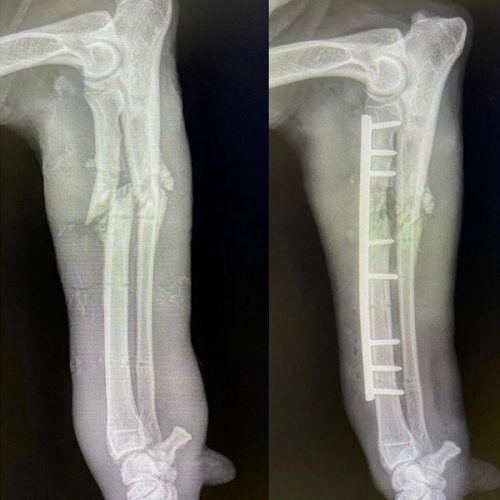

ORTOPEDIA